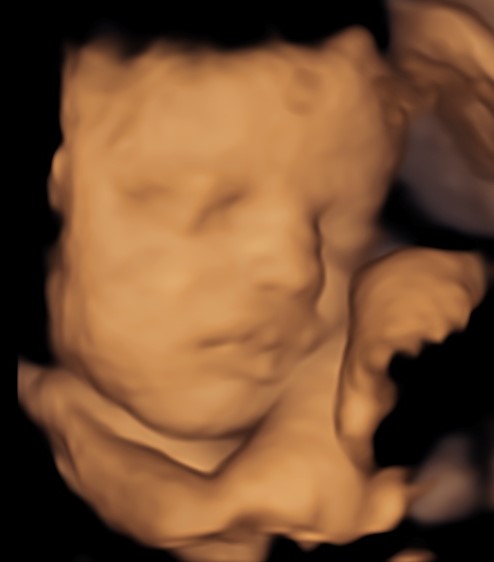

4D/5D/HD Ultrasound Gallery

Gallery